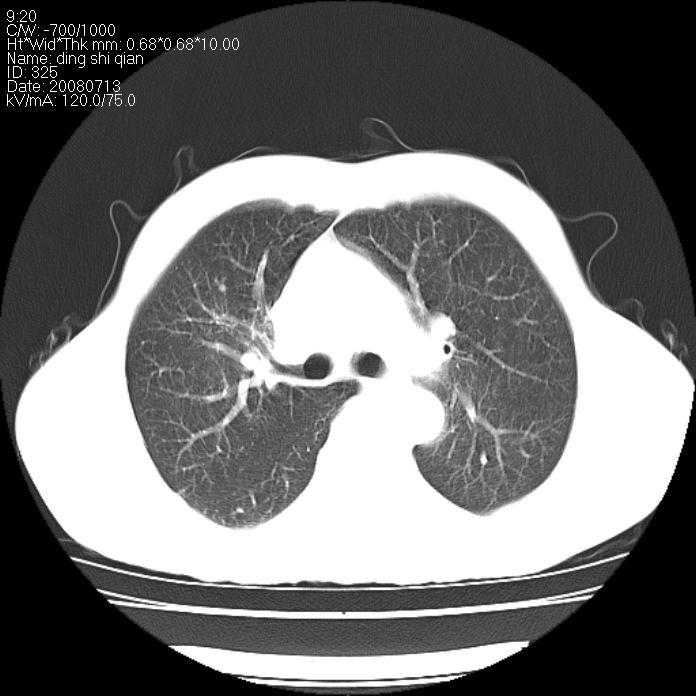

标题: CT14654:男 50岁 近来胸痛 [打印本页]

标题: CT14654:男 50岁 近来胸痛

右侧上肺块状软组织影,浅分叶,边缘毛刺证,与胸膜粘连,考虑:周围性肺癌

右肺上叶周围型肺癌可能性大。

右侧上肺块状软组织影,浅分叶,边缘毛刺证,与胸膜粘连,考虑:周围性肺癌!支持!

典型右肺周围型肺癌

首先考虑周围性肺癌,建议强化或穿刺明确